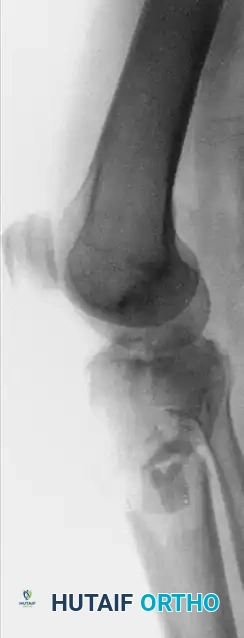

The evaluation of a patient with a suspected tibial plateau fracture demands a systematic, highly disciplined approach. A thorough history must be obtained, focusing on the mechanism of injury—typically an axial load combined with varus or valgus stress—as well as the patient’s overall medical status, physiological age, and functional and economic demands. High-energy trauma (e.g., motor vehicle collisions, falls from height) often results in complex, bicondylar fracture patterns with severe soft tissue compromise, whereas low-energy mechanisms in osteoporotic bone frequently produce isolated lateral depression fractures.

Standard radiographic evaluation includes anteroposterior (AP), lateral, and oblique views of the knee.

For complex bicondylar fractures (Schatzker V and VI), traditional extensile exposures (e.g., Mercedes-Benz incisions or massive single midline incisions with extensive stripping) have historically resulted in catastrophic soft tissue complications, including flap necrosis and deep osteomyelitis.

Severe tibial plateau fractures—characterized by bicondylar involvement, metaphyseal-diaphyseal dissociation, open wounds, or severe closed soft tissue crush injuries (Tscherne II/III)—present a formidable challenge.